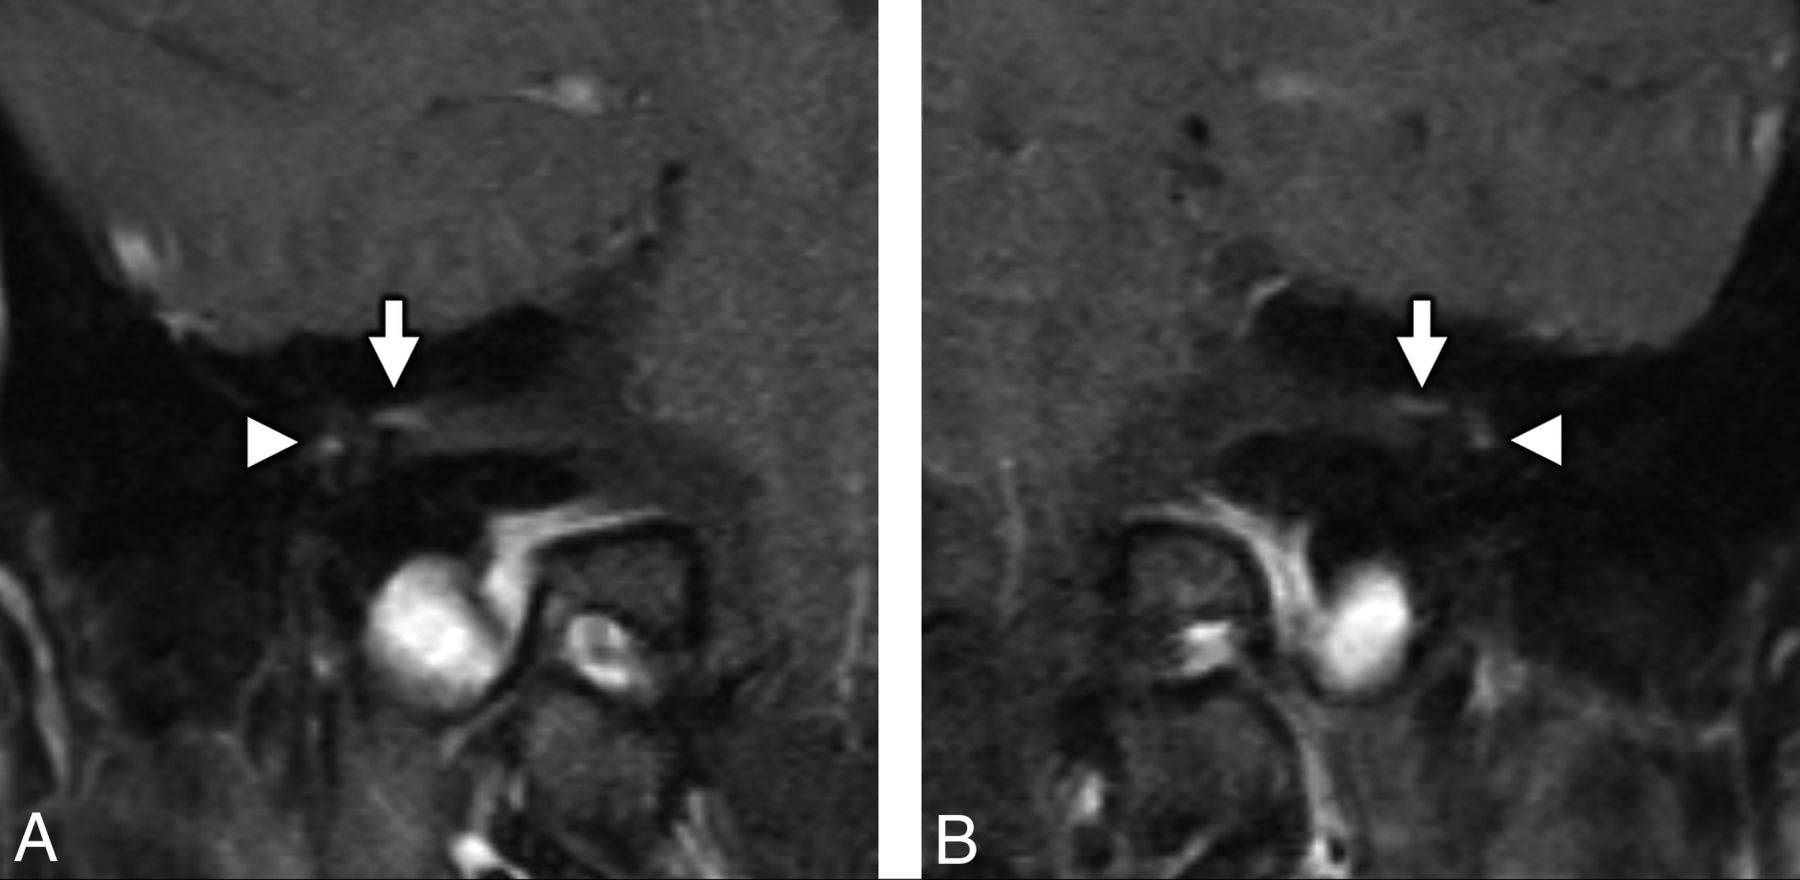

He initially did well with convalescence at home, but on day 16 of illness, he began to experience right-sided facial numbness and weakness. During 24 hours, his symptoms became bilateral and resulted in severe dysarthria, necessitating a return to the emergency department. He also reported associated hypogeusia. Neurologic examination demonstrated a bilateral lower motor neuron pattern of facial weakness with otherwise normal cranial nerve (CN) examination findings, preserved strength and sensation in all extremities, and intact muscle stretch reflexes. He was admitted for observation and underwent MR imaging of the brain and temporal bones, as well as fluoroscopically guided lumbar puncture for CSF sampling. The CSF was negative for bacterial culture and stain and demonstrated normal glucose levels (65 mg/dL), no leukocytes, and mildly elevated protein levels (49 mg/dL). MR imaging demonstrated abnormal enhancement of thefacial (CNVII) and abducens (CNVI) nerves bilaterally, as well as the right oculomotor nerve (CNIII) (Figs 2–4).

MR imaging of the temporal bones in a patient with antecedent COVID-19 and new-onset bifacial weakness and paresthesia subtype Guillain-Barré syndrome. Coronal postcontrast T1-weighted fat-saturated MR imaging of the right (A) and left (B) temporal bones demonstrates abnormal “tuft-like” enhancement at the anterior-superior fundus of the internal auditory canal bilaterally (white arrows), corresponding to the distal canalicular segments of the facial nerves (CNVII). Note additional contrast enhancement along the tympanic segments of the facial nerve bilaterally (white arrowheads), which is greater in degree than typically encountered. Enhancement along the canalicular segments of the facial nerves (white arrows) is always considered abnormal on MR imaging, though mild tympanic segment enhancement is considered within normal limits.

MRI of the brain in a patient with antecedent COVID-19 and new onset bifacial weakness and paresthesias subtype Guillain-Barré syndrome. Axial post-contrast T1-weighted SPoiled Gradient-Recalled (SPGR) MRI shows abnormal enhancement of the right oculomotor nerve (CNIII, white arrow, A), the cisternal segments of the abducens nerves (CNVI) bilaterally (white arrowheads, B), the distal canalicular segments of the facial nerves (CNVII) bilaterally (black arrows, C), and the proximal tympanic segments of the intratemporal facial nerves (CNVII) bilaterally (black arrowheads, C).

Our report details a case of bifacial weakness and paresthesia subtype Guillain-Barré syndrome that was temporally associated with COVID-19. In our case, a patient with antecedent community-acquired COVID-19 pneumonia developed rapidly progressive bilateral facial weakness, extremity paresthesia, and mild proximal extremity weakness without ataxia or other cranial neuropathies 16 days after the onset of COVID-19 symptomatology. He exhibited clinicoradiologic features most consistent with GBS, affecting CNVII bilaterally and lacking antiganglioside antibodies, concordant with prior reports of BFP subtype GBS.8⇓-10 Our patient demonstrated imaging findings that align with prior reports of GBS following antecedent viral infections.11,12 Enhancement of the cranial nerves is a known MR imaging finding in GBS,8,13,14 and most interesting, our patient demonstrated abnormal enhancement of CNVI bilaterally and the right CNIII, which were clinically asymptomatic. On the basis of clinical grounds, we suspect that this indicates subclinical disease in the BFP variant of GBS, rather than the Miller Fisher variant of GBS,15 given lack of ophthalmoparesis and ataxia. Our patient did not demonstrate any typical spinal imaging manifestations of GBS, which may include thickening of the cauda equina nerve roots with enhancement, often with a ventral nerve root predilection.16,17